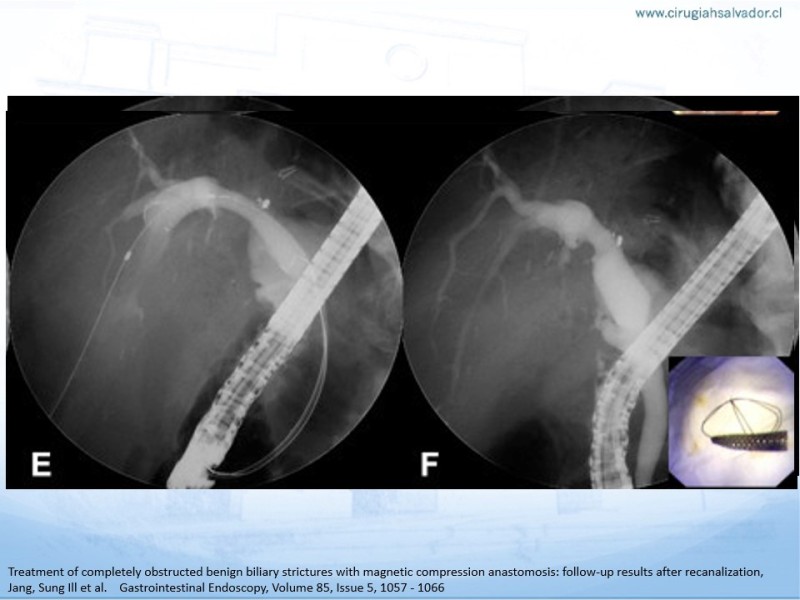

Actualización del drenaje de vía biliar